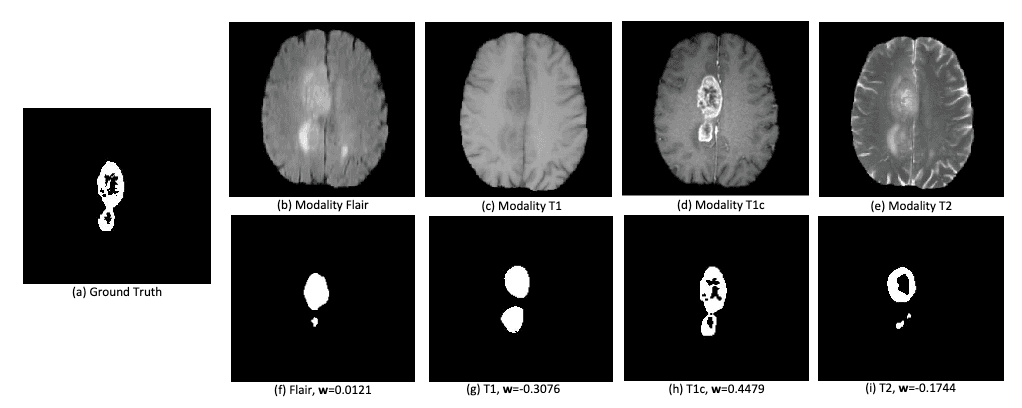

• The BraTS2018 challenge dataset is used to evaluate the model's performance on brain tumor segmentation. This dataset includes MRI scans (T1, T1-contrast enhanced, T2, and Flair) and ground-truth segmentations for three tumor types: enhancing tumor, tumor core, and whole tumor. The task is challenging due to the need to segment and analyze multiple tumor subregions with high precision.

• MCKD demonstrates how the model can handle missing modalities (e.g., missing one MRI modality) by distilling knowledge from the available modalities into the missing ones.